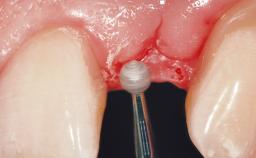

Late Placement of an Implant in a Maxillary Left Central Incisor Site

| Soft Tissue Grafting | Simultaneous |